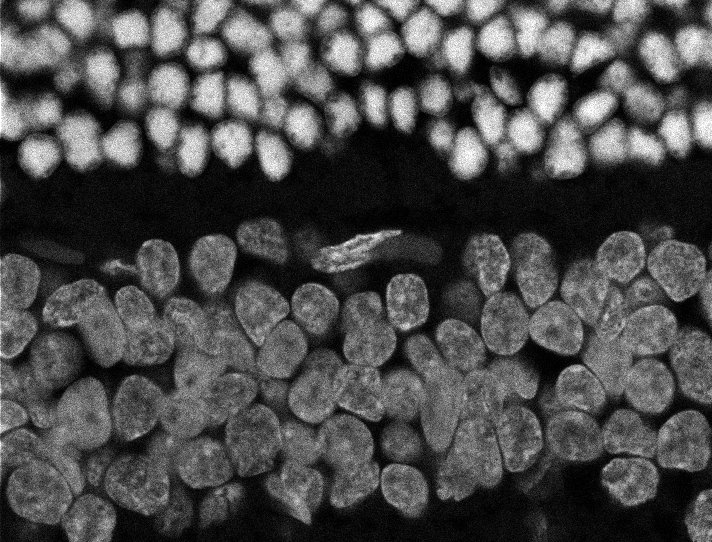

Healthy Eye

Overview 1

Overview 2